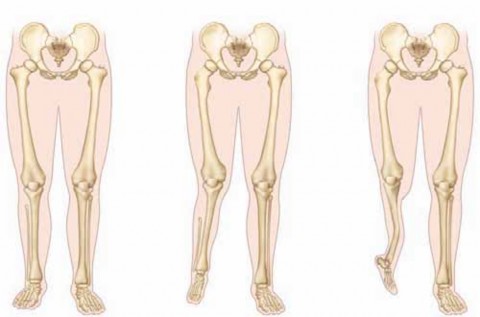

Chapter 38 Syme and Boyd Amputations for Fibular Deficiency Anthony A. Scaduto and Robert M. Bernstein DEFINI…